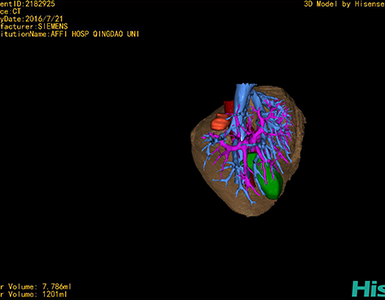

将0.625mm双源薄层CT资料的静脉期和动脉期Dicom格式文件导入海信CAS系统。

通过调节窗宽窗位调整CT序号,对肿瘤,肝实质,胆囊,下腔静脉,肿瘤,肝动脉、门静脉及肝静脉等进行三维重建;系统自动计算肿瘤体积和肝脏体积。

模拟手术操作,自动计算切除肿瘤体积。肝脏体积为1201ml,肿瘤体积为7.786ml,肿瘤体积为肝脏体积的0.6%,通过比对40-50岁正常肝脏体积为1368.38±279.24 ml,肝脏可先进行保守治疗,肾脏进行部分切除术。

术前三维重建:

重建图片